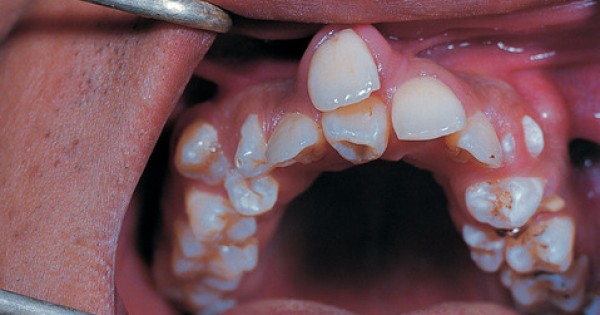

When a person has more than the normal number of teeth- its most likely hyperdontia.

So what's hyperdontia...? It's an oral condition where people have extra teeth growing anywhere in their mouths; often causing complications with the normal eruption of regular teeth, increased tooth decay risk and gum disease.